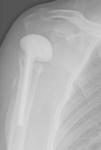

Caso clínicoVarón, 54 años, hepatópata, alérgico a penicilina, que sufre fractura humeral proximal, con angulación cervicodiafisaria de 80° y ascenso troquiteriano de 11mm. Se realiza osteosíntesis con placa Philos (Synthes®) (fig. 1). El paciente comienza la rehabilitación, con arco limitado (60° de abducción activa y 50° de flexión anterior activa), fiebre y seroma en la herida (tamaño ecográfico: 25×12mm), a los 2 meses y 22 días desde la intervención, precisando 2 limpiezas quirúrgicas y toma de cultivos/antibiograma.